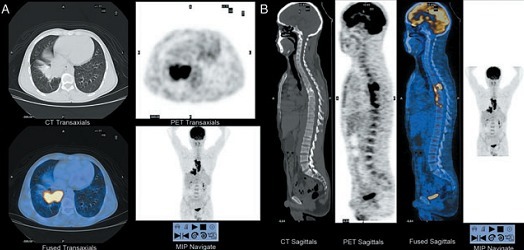

脊椎结核约占所有骨关节结核病例的50%,可发生在任何年龄。20世纪50年代前以儿童为多见,近年来青壮年病例居多,病变多发生在腰椎,随后依次为下段胸椎、胸腰椎、上段胸椎、颈椎和腰骶椎。>>>给医生看一下,我是哪个部位的结核?